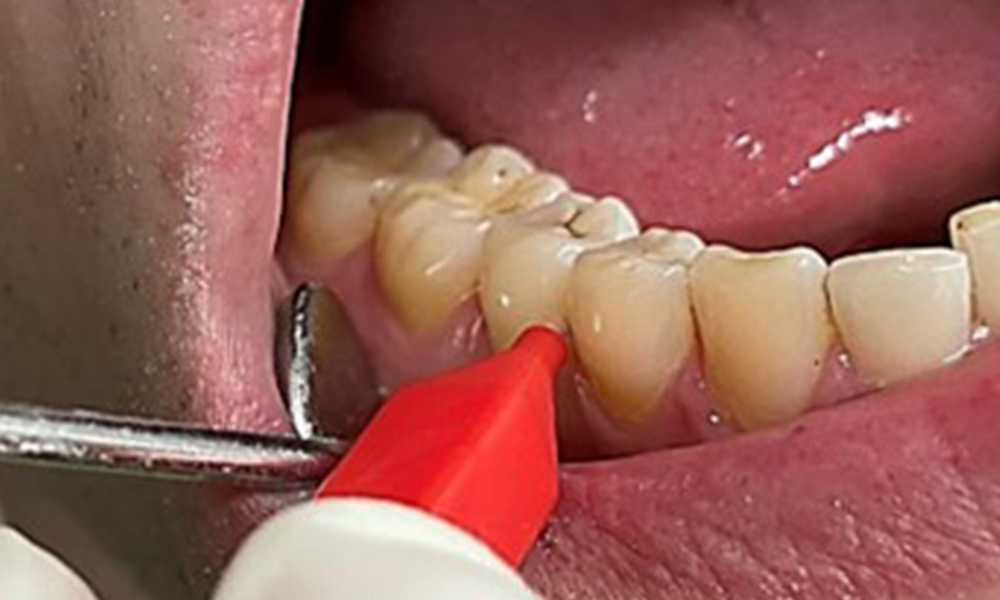

Il est également nécessaire de vérifier que les brosses interdentaires - utilisées quotidiennement par ce patient - sont de la bonne taille et encouragent une utilisation cohérente (Fig. 9). Une bonne hygiène intrabuccale minimise le risque de parodontite lié au tabagisme.

Utilisation des brosses interdentaires dans la zone proche de 44/45

Fig. 9: Utilisation des brosses interdentaires dans la zone proche de 44/45, © Dr R. Krapf